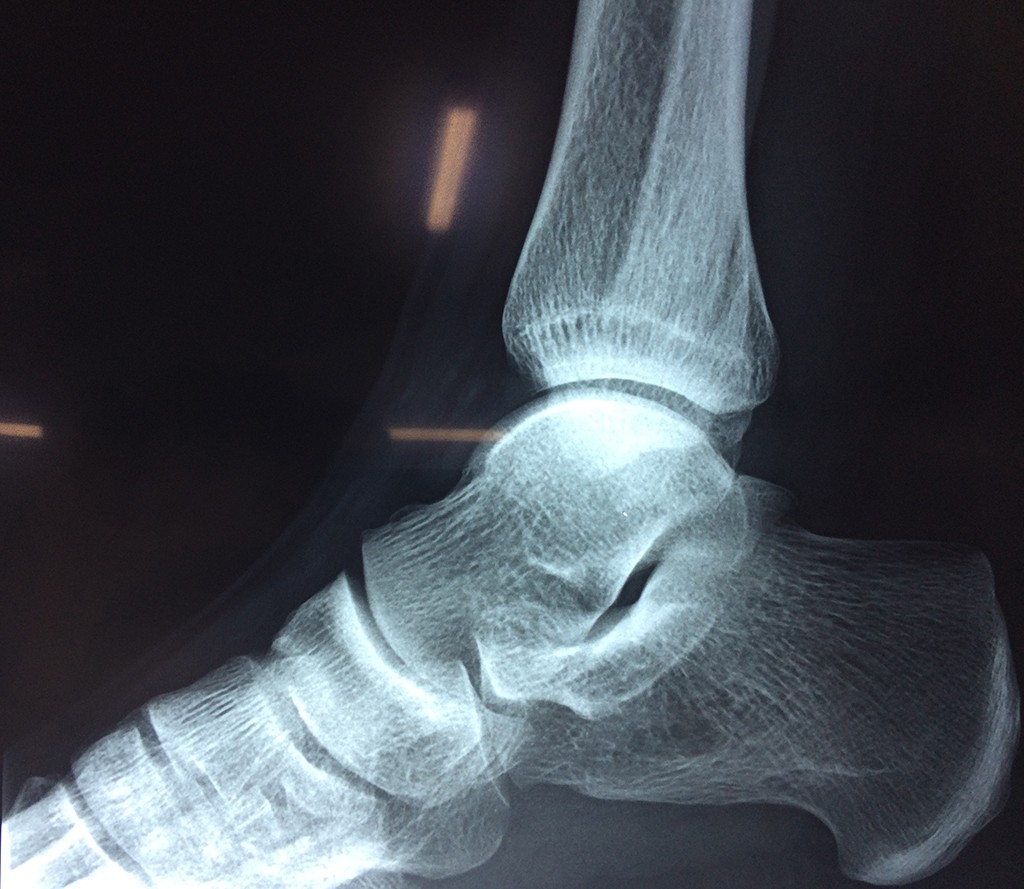

Cirugias en El Salvador - Tobillos

Una fractura de tobillo es la rotura de uno o más de los huesos del tobillo. Estas fracturas pueden ser: